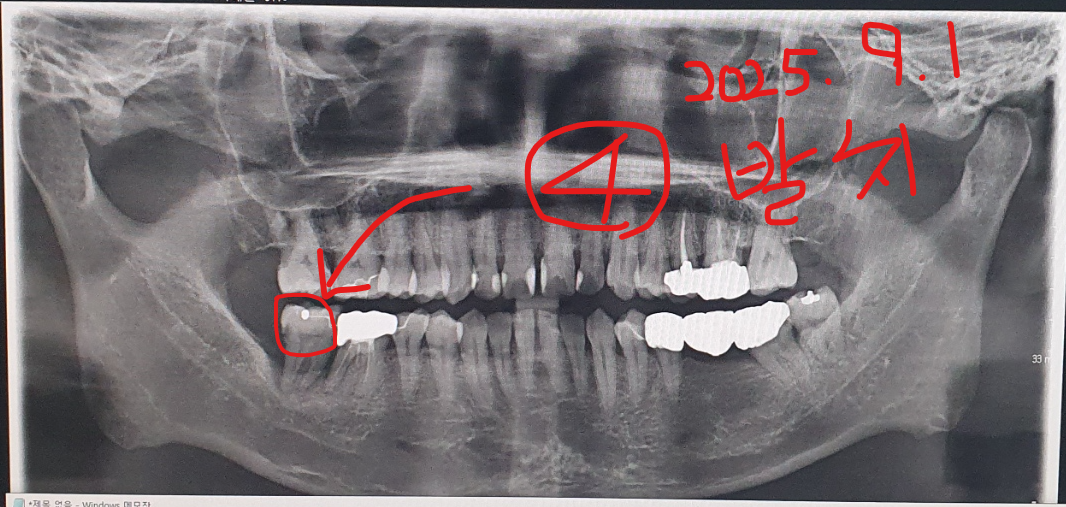

그러인해서 수명도 짧아 질거 같아 걱정되는건 사실입니다. 그리고 첨부사진에 9월1일에 임플란트

하기로했던 어금니 발치전에 9월 1일에 제가 찍어두었던 파노라마 사진(빨간색으로 4번 번호 기재된 사진)입니다.